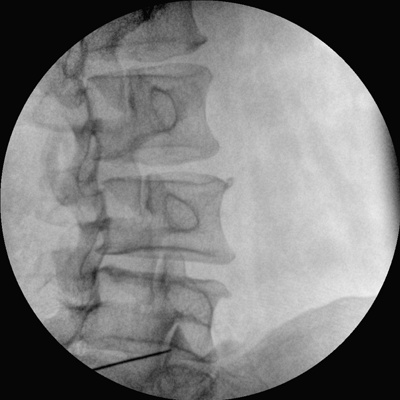

Clinical picture

臨床圖片